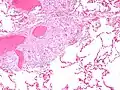

Sarcoidosis in a lymph node

Asteroid body in sarcoidosis